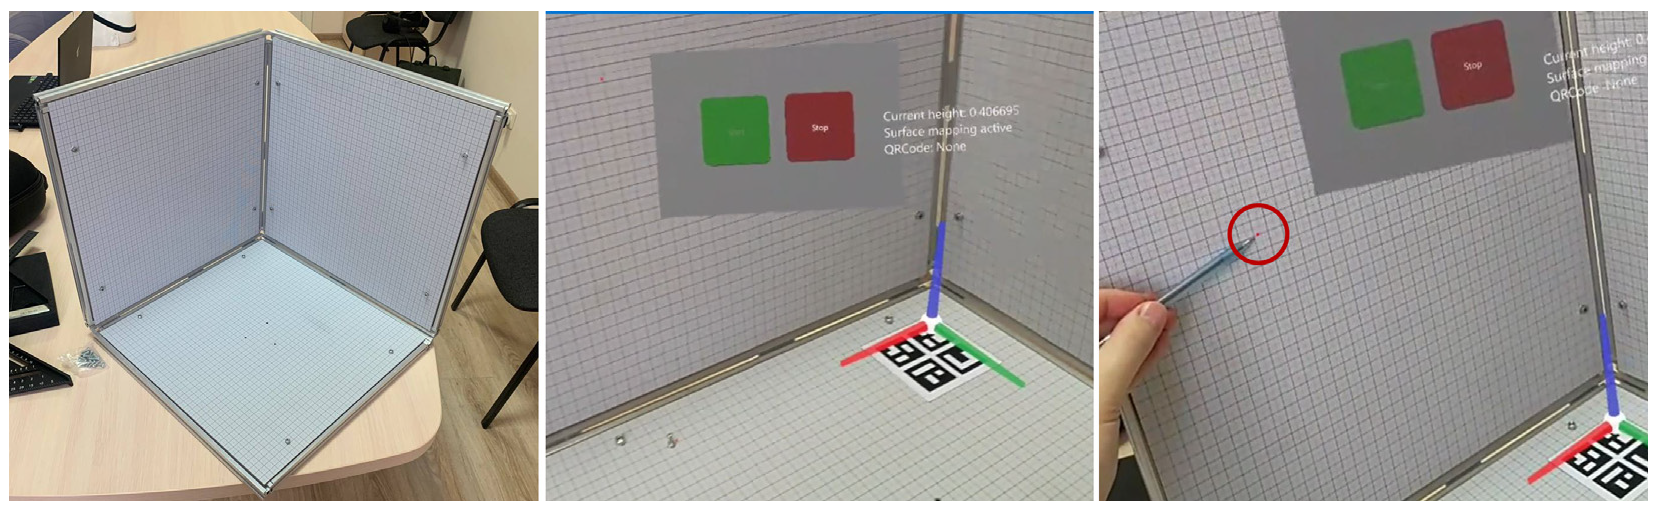

Materials

- Gestures control menu